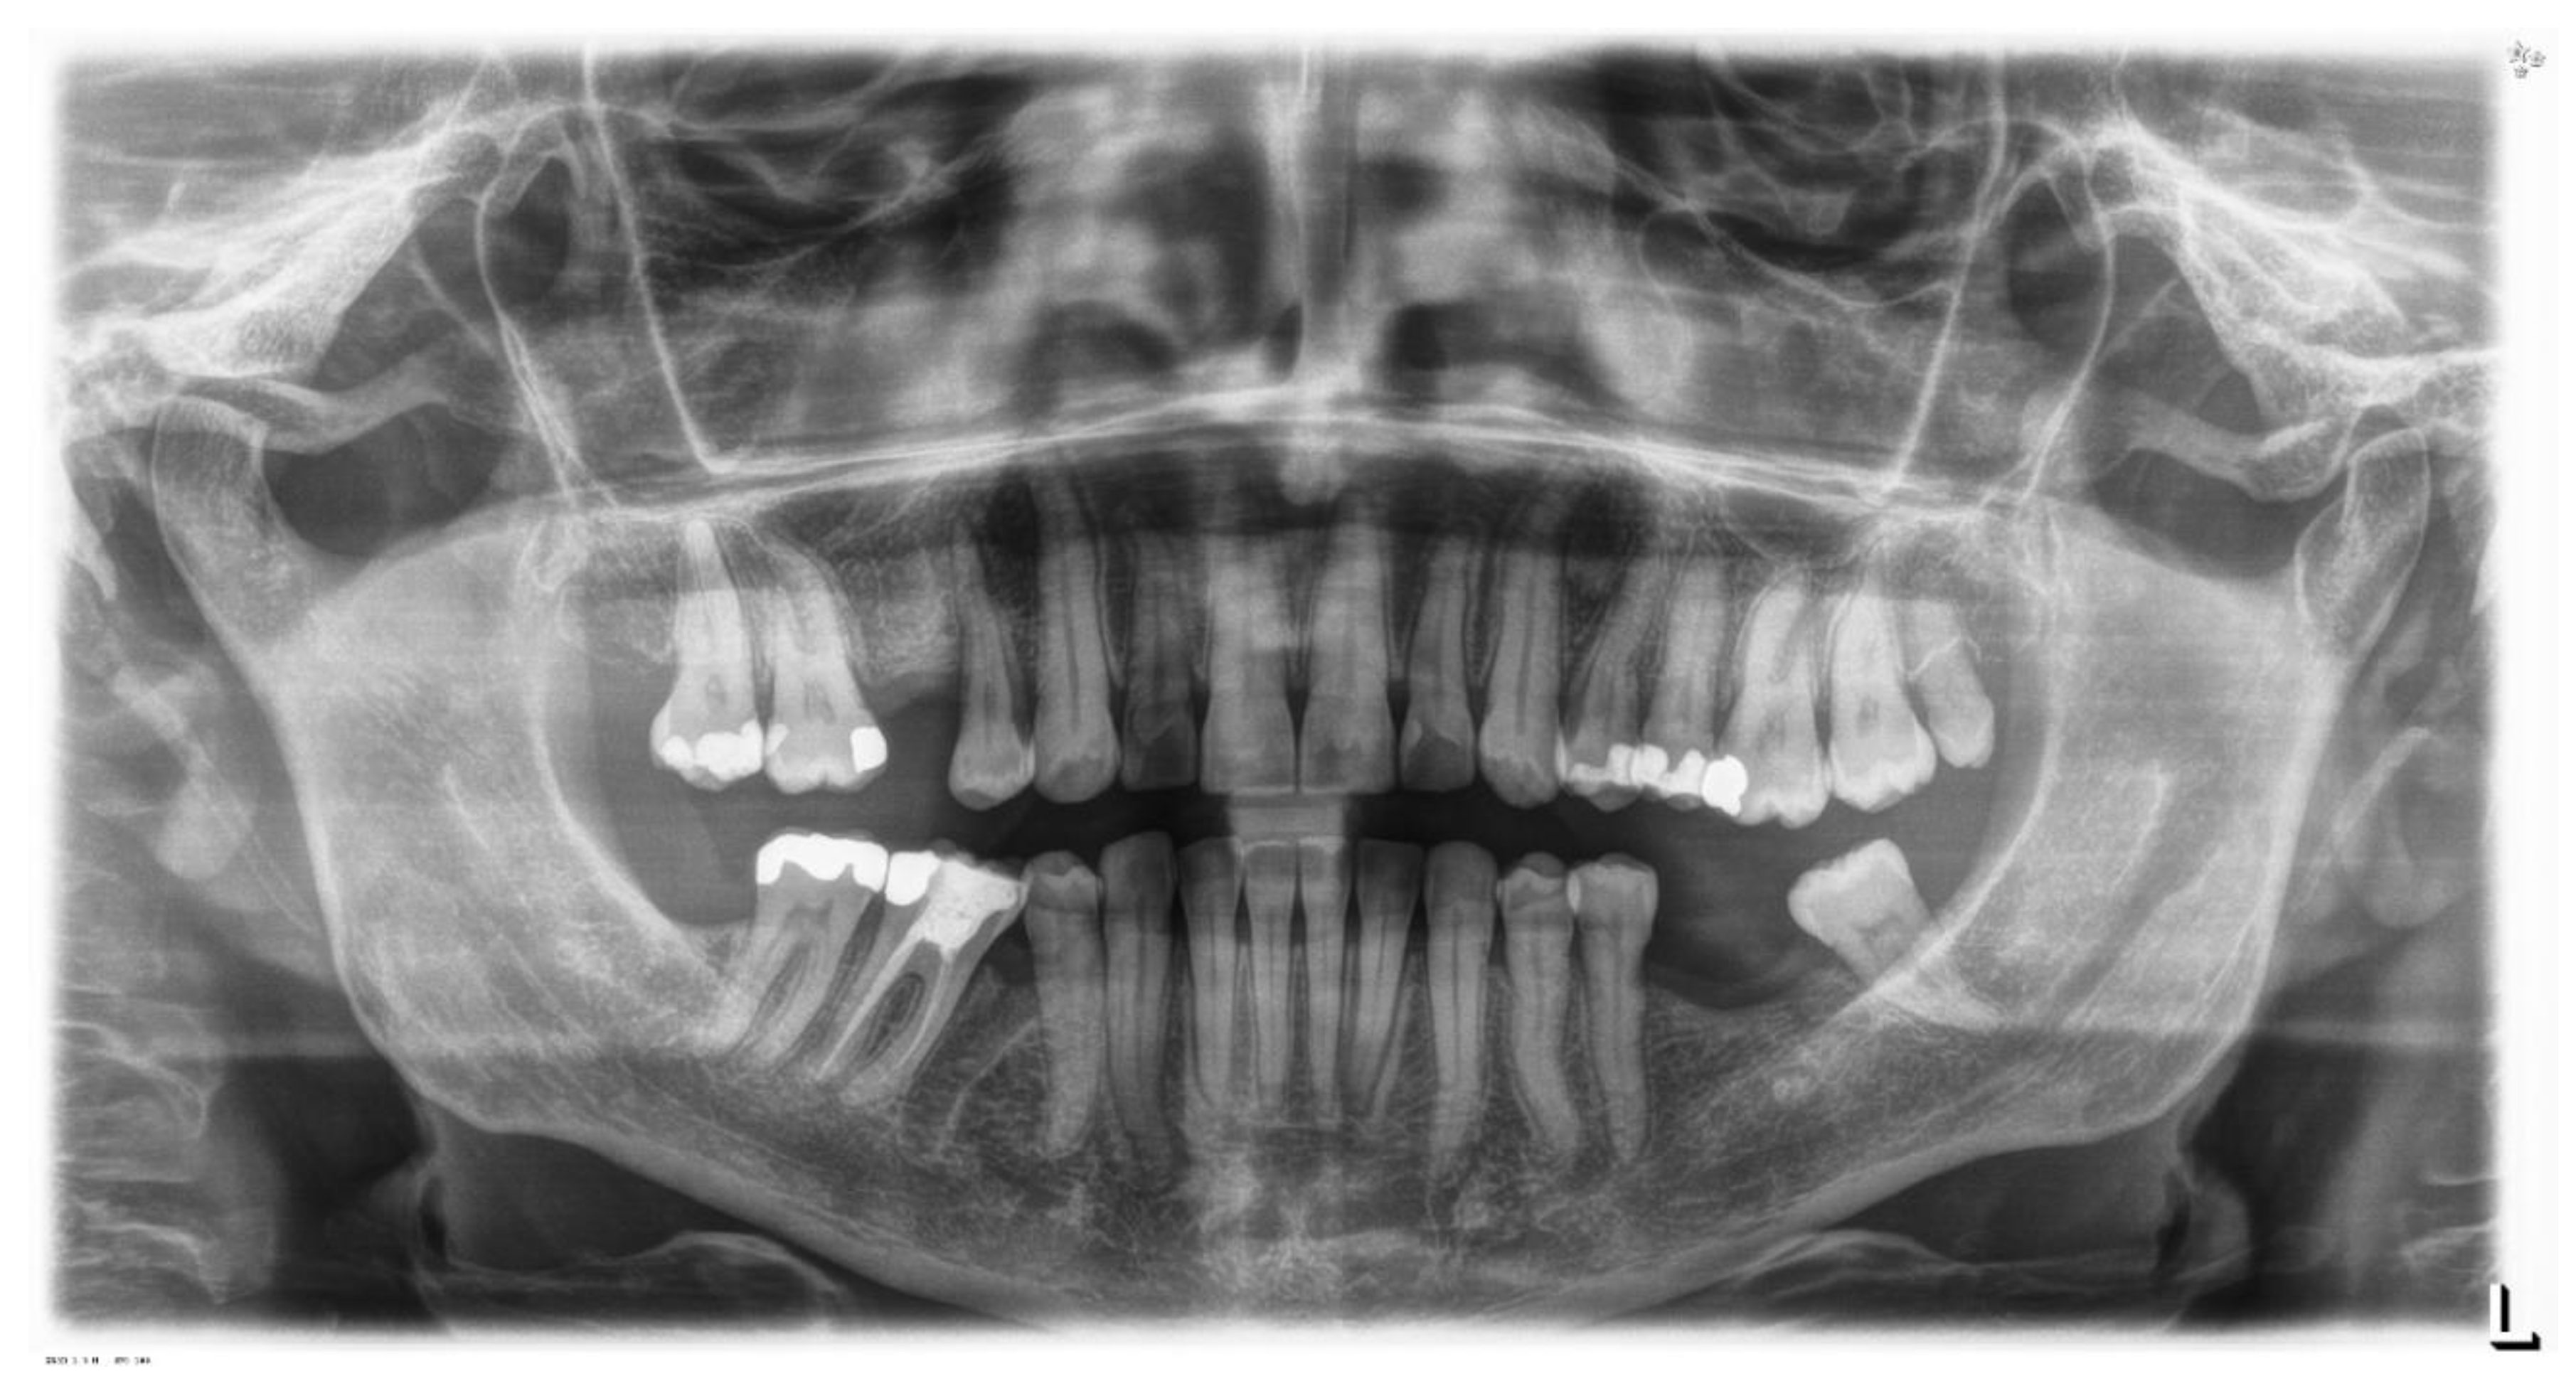

Case 2 concerns a 57-year-old male, with no systemic diseases. He came to our observation in November 2019, to carry out an orthodontic treatment to improve the esthetic appearance of his smile. He showed a good oral hygiene and periodontal condition. Intra-oral evaluation showed a reduction of the transverse diameters, both in the upper and lower dental arches, and a lack of space for the tooth 4.5 in the lower arch (Figure 9 and Figure 10). It was planned to re-establish elements 1.6 and 3.6 after orthodontic therapy in order to reach the first molar class. The most important problem for the patient was related to his smile esthetics and concerned the crossbite of the tooth 2.2.

Figure 9. Pre-treatment orthopantomography.